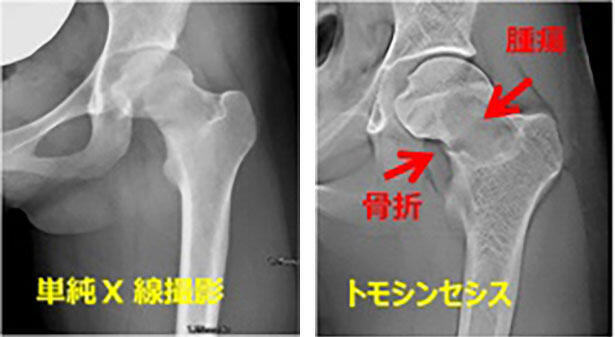

トモシンセシス

2016年6月よりトモシンセシス撮影が可能な最新鋭の透視装置を導入しました。トモシンセシス撮影は、断層画像が短時間で撮影できる最新の画像診断技術です。デジタル断層撮影とも呼ばれています。

最新画像診断技術「トモシンセシス」の特長

• 短時間で撮影ができること

• 被ばく線量が比較的少ないこと

• 金属による影響を受けにくいこと

• 画像が鮮鋭であること

• 当日検査や近日中に検査が可能なこと

主に、整形外科領域の骨折や腫瘍の診断、治療後の経過観察や消化器内科の胆道チューブ抜去の可否の診断に用いられます。

それ以外にも、呼吸器領域・耳鼻科領域・小児科領域など幅広く診断が可能な検査です。